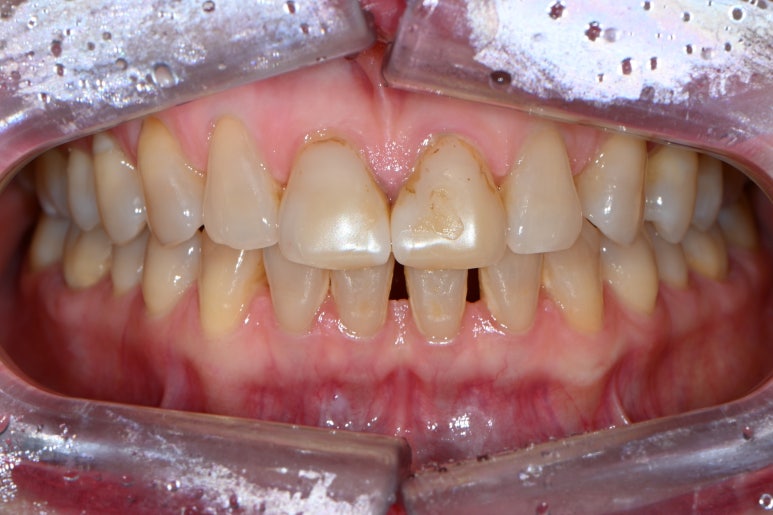

앞니 벌어짐과 앞니 레진 변색을 해결하고 싶은 마음에 압구정 치과에 방문하신 환자분입니다.

잘 보시면, 떼워놓은 앞니 레진 경계가 변색이 되서 갈색으로 보이시는 걸 확인하실 수 있죠??

파란색 빗금친 부위가 대략적으로 레진이 붙어있는 부위입니다.

물론 이만큼 레진으로 치료해내는 것부터 정말 고수이셨을 겁니다.

그렇지만, 시간이 지남에 따라 생기는 레진 변색은 거의 필연적이죠... 결국은 재치료 또 재치료....

빨간색으로 표시된 부위는 가운데 앞니의 빈틈을 메우기 위해 레진을 치아 옆에 붙여놓은 곳입니다.

그래도 요기는 변색은 없네요! 다만 색상의 부조화가 조금 있네요 ^^;;